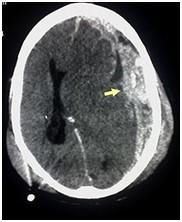

Діагностика

Вдавлений перелом може бути виявлений при хірургічній обробці рани, за допомогою рентгенографії кісток черепа, і краще за все діагностується при виконанні комп’ютерної томографії голови.